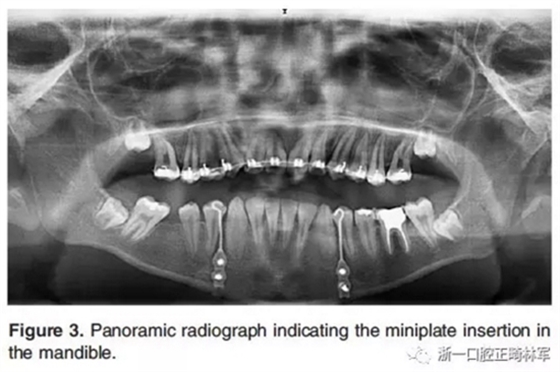

然后在全身麻醉下對所有患者進(jìn)行手術(shù)。在手術(shù)的第一步,在下頜兩側(cè)尖牙和第一前磨牙之間放置鈦板,并固定一個牽引鉤,位于尖牙和第一前磨牙的鄰間隙(Figure 2a,F(xiàn)igure 3)。手術(shù)的第二步,進(jìn)行不完全的Le Fort I截骨術(shù)以釋放上頜骨(Figure 2b)。Le Fort I截骨術(shù)中包括上頜骨的鼻腔外側(cè)壁,但鼻壁和鼻中隔保持完整,不包括翼板。